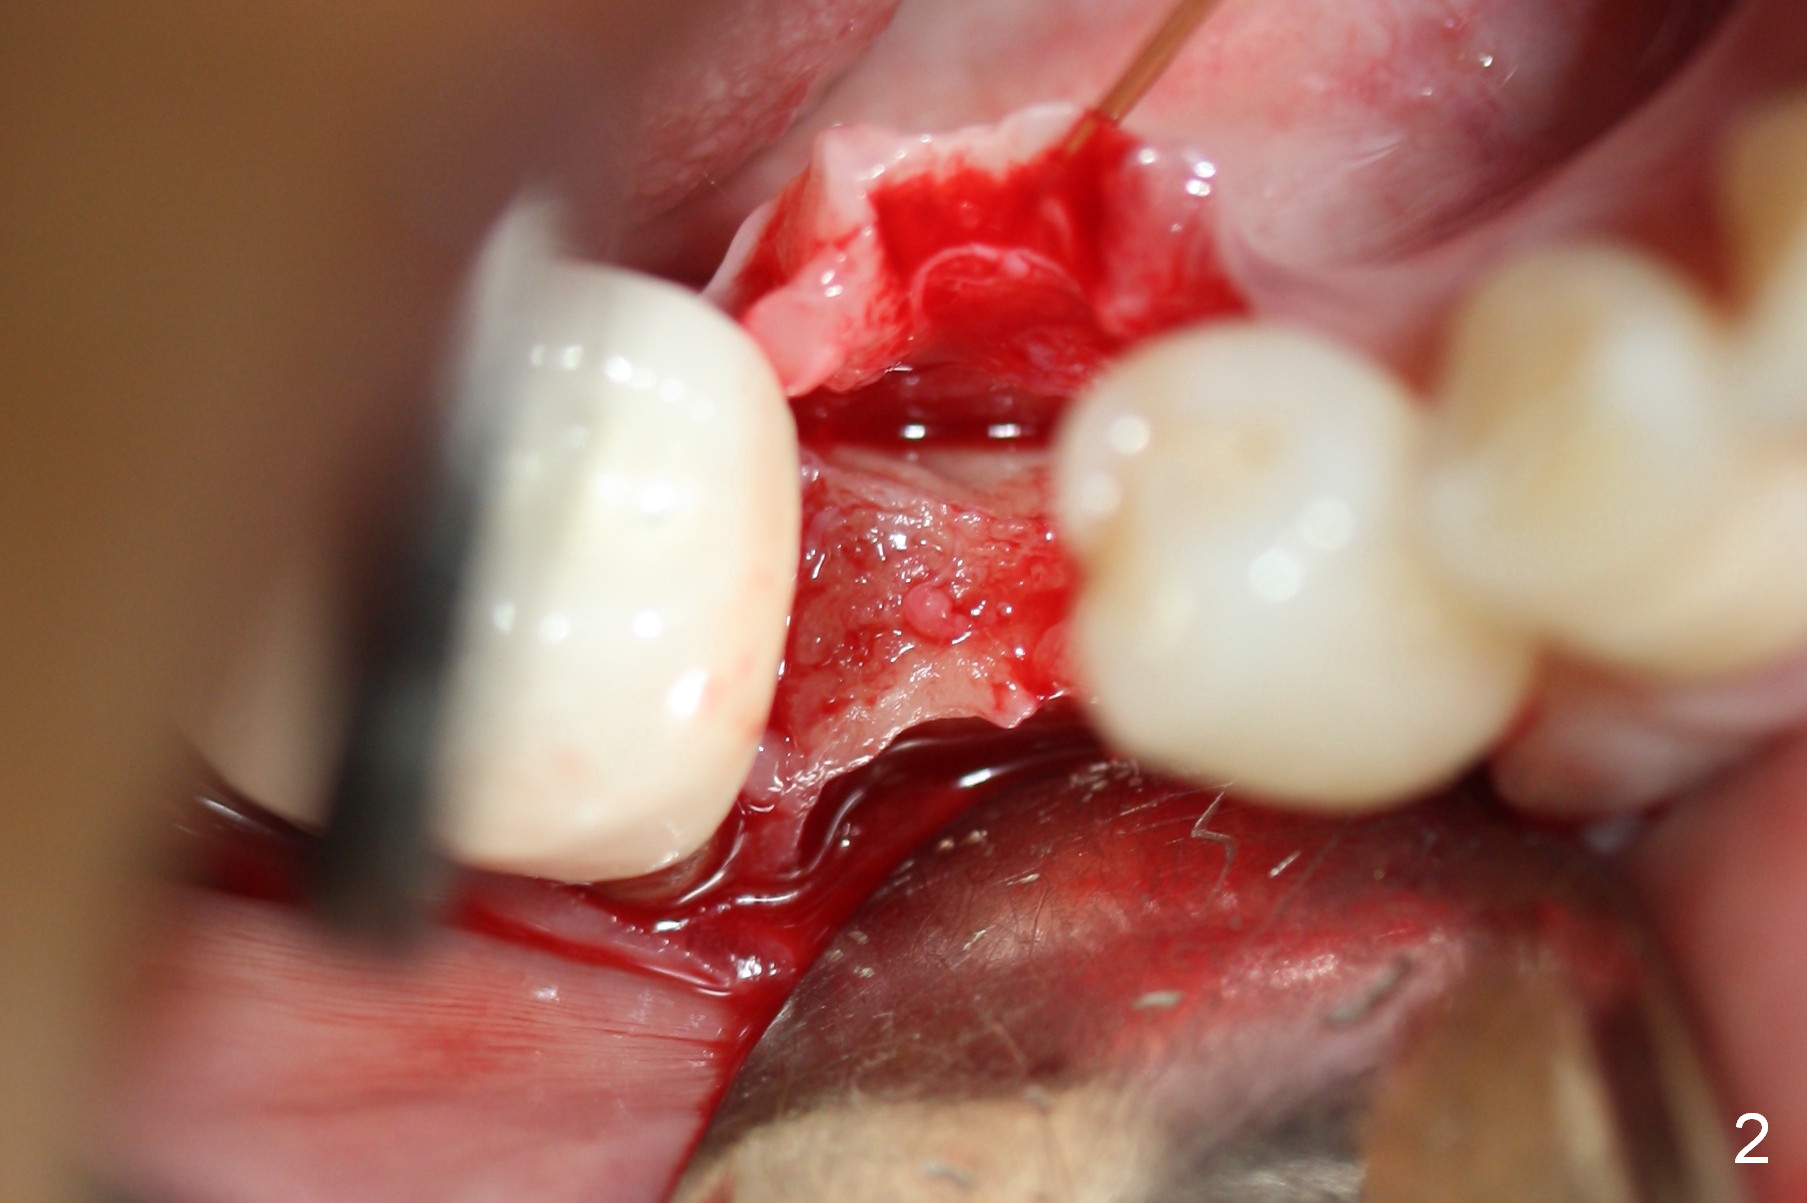

Preop photo shows the distal inclination of the tooth #28 (Fig.1).  The distal surface of the latter is reduced before incision for implant placement at #29 (Fig.2).  The buccolingual width is approximately 4 mm, as compared to 3 mm implant positioner (Fig.3).  After 1.2x10 mm osteotomy (Fig.5), the mesiodistal cortical bone is removed with a small high-speed fissural bur (Fig.4).  When a 2.5x12(2) mm 1-piece implant is placed (Fig.6), there is no buccal (Fig.7) or lingual plate perforation.  There is no postop paresthesia.  There is mild bone loss distal 4 months postop (Fig.8 *).  Take photos before and after permanent crown cementation to show increase in ridge width after bone graft and improvement in gingival health after provisional modification.  Take PA and/or BW post cementation to show that the distal bone resorption (Fig.8 *) is partially due to angulation.  No continuous bone loss 15 months post cementation (Fig.9).  There is mild bone resorption mesially 2 years 3 months post cementation (Fig.10).  The soft and hard tissues remain healthy 4 years 3 months post cementation (Fig.11,12).